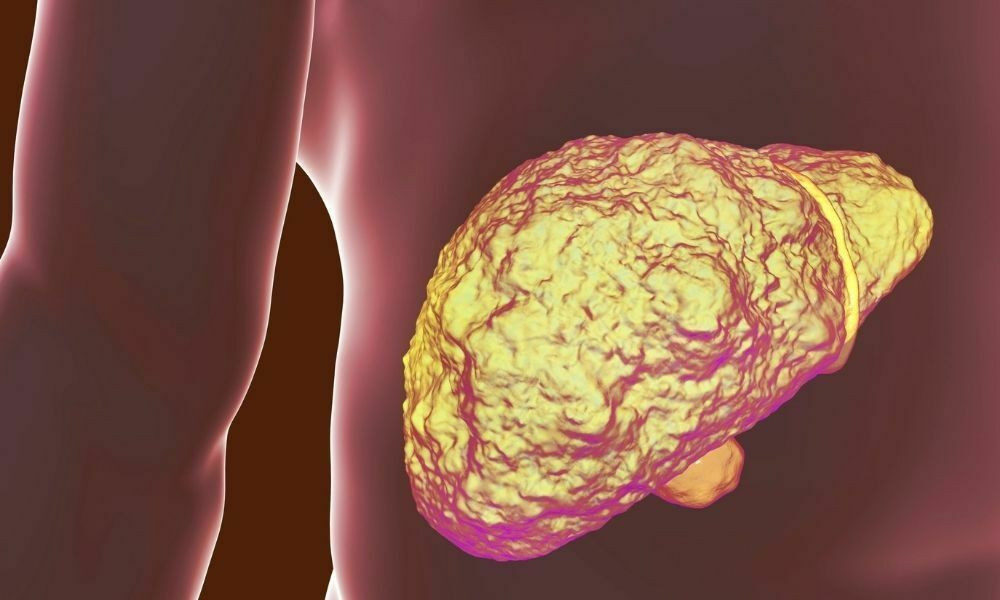

Kronik karaciğer hastalığı, halk arasında yaygın bilinen adıyla siroz, karaciğerde oluşan hasarlar ile doğrudan ilgilidir. Çeşitli hastalıkların yan etkisi olarak veya yoğun ilaç kullanımı karaciğerde hasarlanmalara yol açabilir. Karaciğerde oluşabilecek çok küçük bir sorun, vücut sağlığı açısından büyük sonuçlar doğurabilir. Karaciğer her hasar aldığında kendini onarır ve sert bir yara dokusu meydana getirir. Karaciğerde çok fazla yara dokusu meydana geldiği zaman organ işlevsel özelliklerini kaybetmeye başlar. Yaralı doku karaciğerin tamamına yayıldıkça ve hücreler öldükçe siroz hastalığı ortaya çıkar.

Kronik karaciğer hastalığı ölümcül sonuçları olabilen bir hastalıktır. İlerlemiş karaciğer hasarlarında ne yazık ki geri dönüşü olmayan sorunlar meydana gelebilir. Vücudun sağlıklı bir yaşam sürmesinde çok önemli görevleri bulunan karaciğerin tamamına yayılan siroz hastalığı bu organın işlevini bozar. Karaciğer işlevini kaybedince vücuttaki pek çok görevini yerine getiremeyeceği için ölüm riskini meydana getirebilir. Bununla birlikte ilerlemiş seviyedeki karaciğer hastalarına doktor önerisi ile karaciğer nakli yapılmaktadır.

Kronik karaciğer hastalığının seviyeleri, A, B ve C olacak şekilde 3 seviyedir. Siroz hastalığının ilerleme seviyesine göre farklı tedavi yöntemleri uygulanmaktadır. A ve B seviyesi siroz hastaları henüz başlangıç seviyesi olarak görülebildiği için bu kişilerde karaciğerde aşırı hasar söz konusu değildir. Tedavilerle hastalığın ilerlemesi en aza indirilir ve siroz hastaları da kaliteli bir yaşam sürebilir.